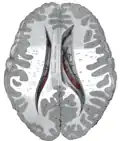

Il s'enroule d'avant en arrière autour du thalamus où il forme la paroi latérale des ventricules latéraux, s'incurve au niveau du pulvinar, sous le splenium du corps calleux, et se réfléchit d'arrière en avant au sein du lobe temporal, au-dessus de la corne temporale du ventricule latéral, pour se terminer en arrière de l'amygdale cérébrale.

Coronal section through anterior cornua of lateral ventricles.